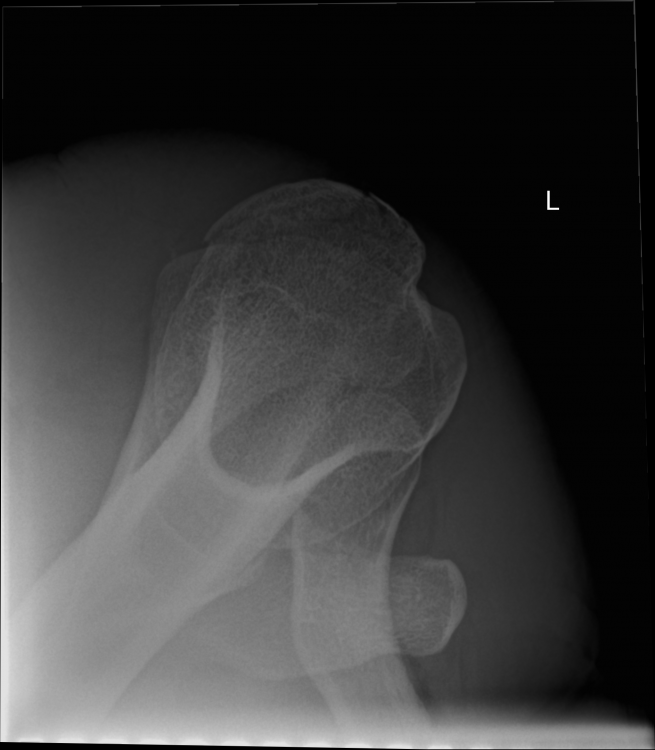

3. Röntgen am Unfalltag: --- MRT nach 6 Wochen (die Bilder habe ich selbst am PC gemacht - mein Arzt hat sie mir vorher gezeigt): --- Röntgen nach 12 Wochen: